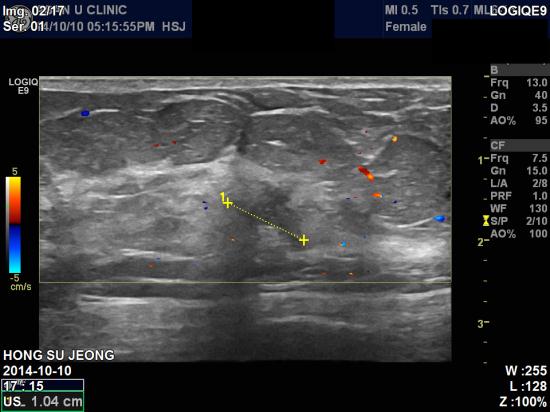

상기환자 건강검진으로 유방촬영 후

좌측 유방 종괴소견으로 내원하신

56세 여성분 이십니다.

본원 초음파상 좌측 3 : 30분 방향으로 1.04cm혹있어,

조직검사 시행하였으며

조직검사 결과상 좌측  침윤성 유관암으로 진단되었습니다.